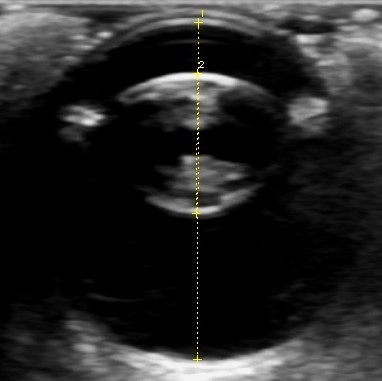

当院では各種眼科検査(涙液量検査・眼圧検査・細隙灯検査・眼底検査・眼超音波検査など)に対応し、一般外来および他の動物病院からの紹介も承っております。